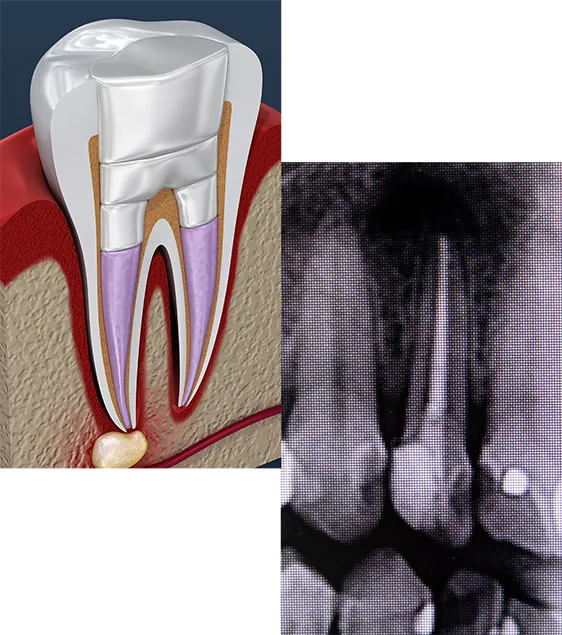

By removing the infected inner tissue—the pulp—of the tooth with a root canal, we both treat the current infection and help prevent a future infection. Since an infection can spread to other tissues surrounding the infected tooth, immediate action is important.

The root canal process begins by drilling a small hole in the tooth, through which the dentist removes the inner pulp. The dentist then seals this hole, or may choose to restore the tooth with a dental crown. Since we give every patient a local anesthetic before treatment—just like with fillings—patients typically don’t feel a thing.